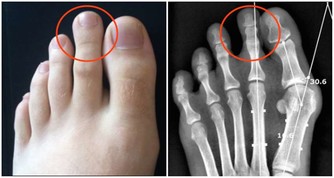

筋縮就是伸縮範圍減小了,原來能拉一米的筋現在只能拉至半米了。筋縮的“筋”從病理上看,有纖維化、粘連、瘢痕形成、增厚、腫脹,有老百姓所說的“筋疙瘩”形成。這種“筋疙瘩”即筋結。“身有千千結”,這千千結就是我們身上的筋結。

觸摸有筋結的部位,會感覺緊張、僵硬、痙攣、腫脹,會摸到增厚甚至“筋疙瘩”,壓痛明顯;

從功能上看,筋結會使關節活動範圍減小,轉頭受限,彎腰困難,抬腿彎膝不如從前。筋結壓迫神經造成疼痛,壓迫血管造成供血不足,筋脈失養,麻木抽搐,以及內科疾病等一系列病症……